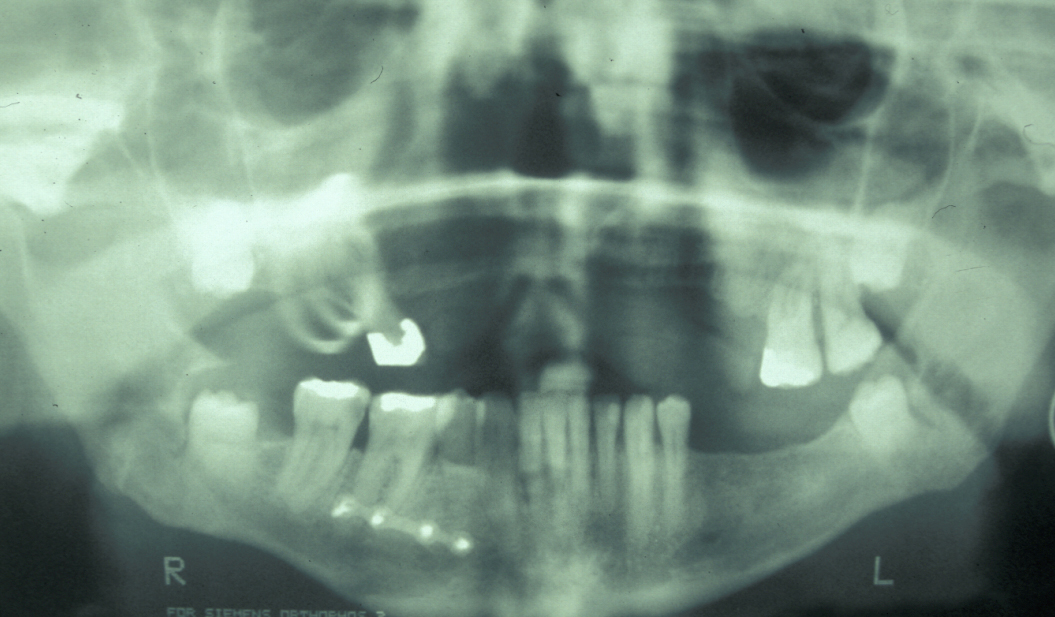

The combination of plain X-ray radiographs taken from different directions gives adequate diagnostic information for most mandibular fractures (DPT, dental panoramic tomogram (see Figure 2) and posteroanterior radiographs (see Figure 3)).

Figure 2: Dental panoramic tomogram showing bilateral mandibular angle fractures. Note the previous repair of a parasymphyseal fracture with a single body plate.

Figure 3: Posteroanterior radiograph of bilateral mandibular angle fractures. Same case as in Figure 2.